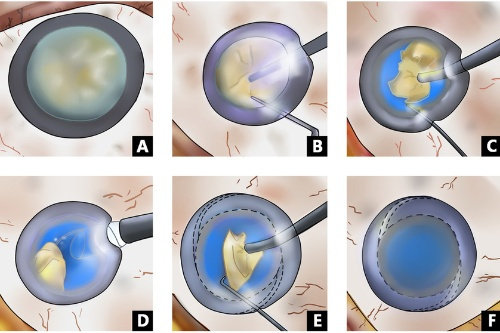

作为强生眼力健基于TECNIS平台研发的第三代无级变焦晶体,它突破传统单焦点、多焦点晶体的局限,通过创新光学设计实现远中近视力无缝衔接,同时覆盖近视、散光、老花眼矫正需求。

传统多焦点晶体依赖衍射环分割光线,易产生光晕干扰;艾无极采用高阶渐进折射技术,光学区度数从周边向中央平滑递增,形成连续焦深,实现33厘米至无限远的平滑过渡。

手术费用涵盖超声乳化技术、飞秒激光辅助等选项。

采用疏水性丙烯酸酯材料,降低术后后发性白内障发生率。

手术操作便捷性:预装式设计缩短手术时间。